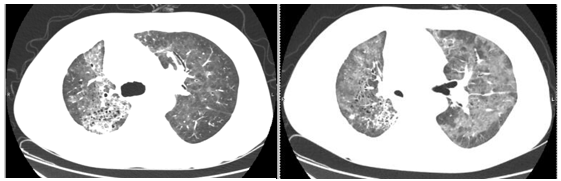

体检时医生给我查的胸部低剂量CT是什么东东? 胸部低剂量CT一般用于肺癌筛查,外院发现肺结节,做进一步确诊的时候就要做常规CT的检查了。 &l...